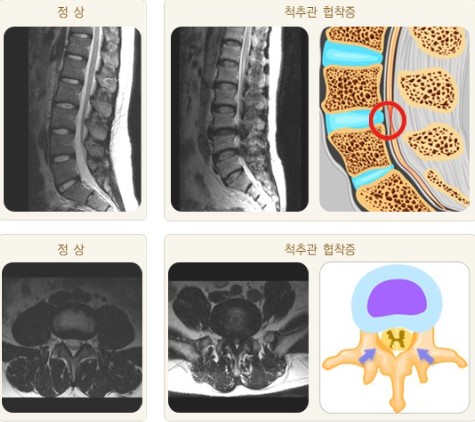

오늘 글에서는 척추관 협착증 증상 치료방법에 대해서 알아보도록 하겠어요. 척추관 협착증은 퇴행성 디스크와 아울러 전형적인 퇴행성 척추질환입니다. 척추의 퇴행이 오래 진행되어 인대가 두꺼워지고 붓게 된다면 신경구멍이 좁아지며 척추관 협착증이 유발되요.

척추관 협착증 원인

척추 관절과 인대가 변경되고 두꺼워져 척추 신경을 조이면 신경의 혈액순환이 모자라게 되어 생겨해요. 선천적으로 요추관의 정도가 정상보다 작게 만들어지는 경우로, 대개는 35세가 넘어 뼈와 인대의 변환가 연거푸해서 증상이 형성되나 20세 전후의 아주 젊은 나이에도 띄엄띄엄 발견되요.

최고 많이 보이는 원인으로 척추 퇴행성 골관절염이 생김에 따라 허리 관절의 정도가 많아지고 인대도 두꺼워지는 더불어 가시 같은 뼈가 자라나 신경 길을 좁아지게 해요.

척추관 협착증은 척추 관절과 주변 조직의 변화로 인해 나타나는 질환입니다. 이 질환의 원인은 자연적인 단계인 노화로 인한 척추 관절 연골 파괴와 뼈 형태적 전환, 디스크의 노화나 손상, 척추 골절, 척추 관절 염증, 그리고 선천적인 이상 등 각가지 요소들이 복합적으로 활동하여 생겨날수 있고요.

이러한 요소들은 척추관의 좁아짐과 신경 구조에 압력이 가해짐으로써 척추관 협착증을 일으킬 수 있습니다. 개인의 생활 습관, 유전적 요인, 부상 등도 사유로 작용할 수 있으며 각 개인의 경우에는 이러한 요소들이 복합적으로 작용하여 질환을 촉발합니다.